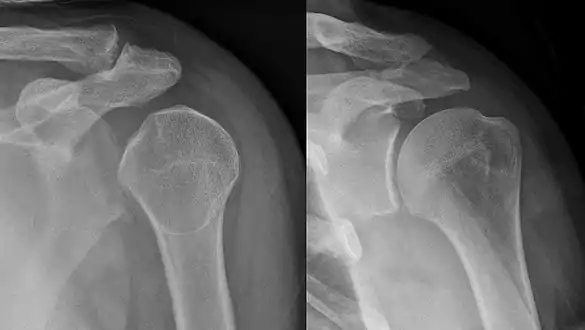

Shoulder dislocation before (left) and after (right) being reduced